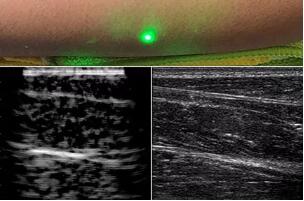

目前,研究人員已經(jīng)與健康的志愿者測試了他們的系統(tǒng):從半米遠處掃描了他們的前臂,并將這些結果與傳統(tǒng)超聲的結果進行了比較。他們能夠觀察到深達6厘米的組織,并能看到肌肉,脂肪和骨頭,并報告其結果可與標準超聲相媲美。

研究人員用一種激光裝置測試了這個想法,該裝置使用一個波長為1,550納米的脈沖激光來產(chǎn)生聲波,并使用第二個連續(xù)激光,調(diào)諧到相同的波長以遠程檢測反射的聲波。第二個激光器是靈敏的運動檢測器,可測量聲波從肌肉,脂肪和其他組織反射回來而引起的皮膚表面振動。反射的聲波產(chǎn)生的皮膚表面運動會導致激光頻率發(fā)生變化,這種變化可以測量。通過機械掃描人體上的激光,科學家可以獲取不同位置的數(shù)據(jù)并生成該區(qū)域的圖像。